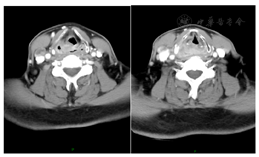

患者下咽鳞癌局部晚期,经综合查房后决定行新辅助治疗方案帕博利珠单抗100 mg ivgtt d1联合紫杉醇脂质体300 mg ivgtt d1及顺铂120 mg ivgtt d1,Q21d,患者分别于2021年11月29日、12月20日、2022年1月10日行3周期新辅助治疗。治疗3周期后评估,右颈淋巴结较前明显减小,已不具体。疗后颈部影像评价:右侧梨状窝处软组织增厚,局部形成肿物,边界不清楚,较前缩小,最厚处仍约0.6 cm,侧颈中深淋巴结较前明显缩小,现最大短径约0.6 cm(图3)。疗后喉镜:下咽部右侧梨状窝内部肿物基本消退,表面基本变平,环后区黏膜显水肿,余下咽部基本平整。声带活动正常(图4)。总体疗后评价MPR。常规复查血常规,血生化,心肌酶等未见明显异常,超声心动、心电图未见异常,无主观特殊毒性反应报告过程中监测类风湿因子,肝肾功能正常。患者于新辅助治疗结束后第5周(2022年2月16日)行右侧梨状窝扩大切除锁骨上皮瓣修复 右颈Ⅱ~Ⅳ区 右颈Ⅵ区清扫 气管切开术,过程顺利。